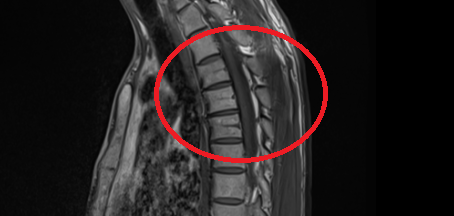

척추 mri를 찍어서 봤는데 저런식으로 홈이나 금간것저럼 보이는게 있는데 저건 뭔가요???

뼈에 금이 간게 아니라면 뭔지 궁금합니다

이런 경우에 골절이 아닌지 오해하시는 경우가 많은데 골절이 아닙니다.

골절의 경우에는 T1 영상에서 조영이 떨어지고 fat suppression T2 영상에서 조영이 증가하는 소견을 확인해야합니다.

골절이 아니면 왜 저렇게 보이는지 까지는 제가 잘 모르지만 저 소견을 이상소견으로 보이는 않습니다.